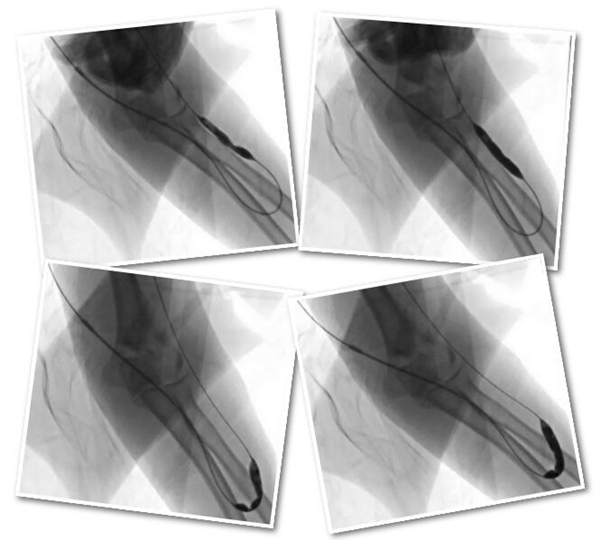

导管室无影灯下,陈力强和赵庆和主任小心地将仅两毫米粗细的鞘管插入王老先生的肱动脉,再顺鞘管送入导丝进行导管造影,发现造瘘动脉中段以下完全闭塞,里面充满血栓。

在血栓处缓慢注射尿激酶溶栓治疗后,动脉血流少量恢复,但里面仍见大块血栓,局部明显狭窄。

此时,两位主任发现,正是由于糖尿病动脉硬化等原因造成血管狭窄,血流变慢逐步形成血栓,最终堵塞血管。找到罪魁祸首之后,两位主任想尽办法将扩张球囊送到狭窄段,将三个狭窄段完全扩张。

再次造影血流通畅很多,局部仅见两个较大血栓, 决定带鞘管继续溶栓。

一番紧张忙碌之后,回到病房时已是华灯初上,胸外科马振东主任仍在等待,在交代完护理要点、安排完溶栓事宜后才安心回家。次日,经过一夜持续局部溶栓之后,再次造影发现血栓消失,血流非常通畅,血管也恢复了正常搏动,手术宣告成功。